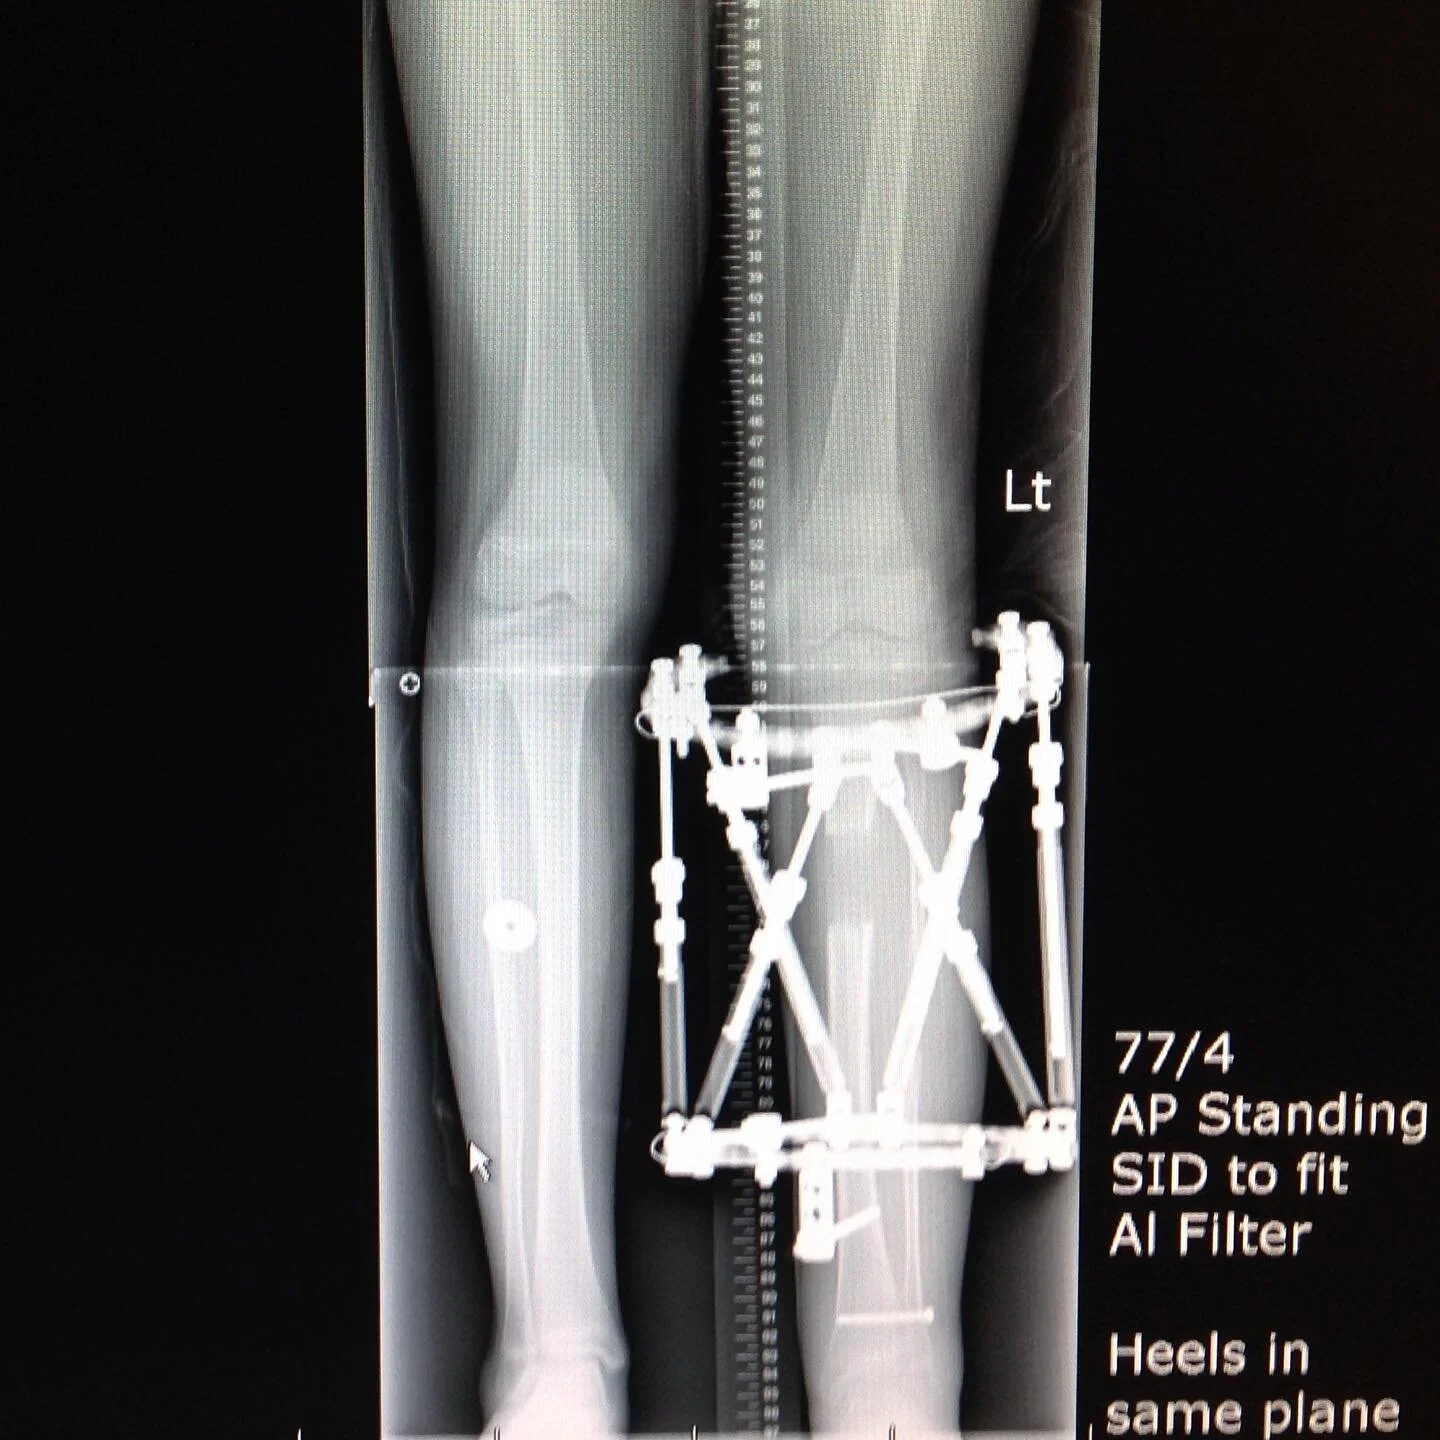

Limb Lengthening and Reconstruction Program

BC Children's Hospital Department of Orthopaedics